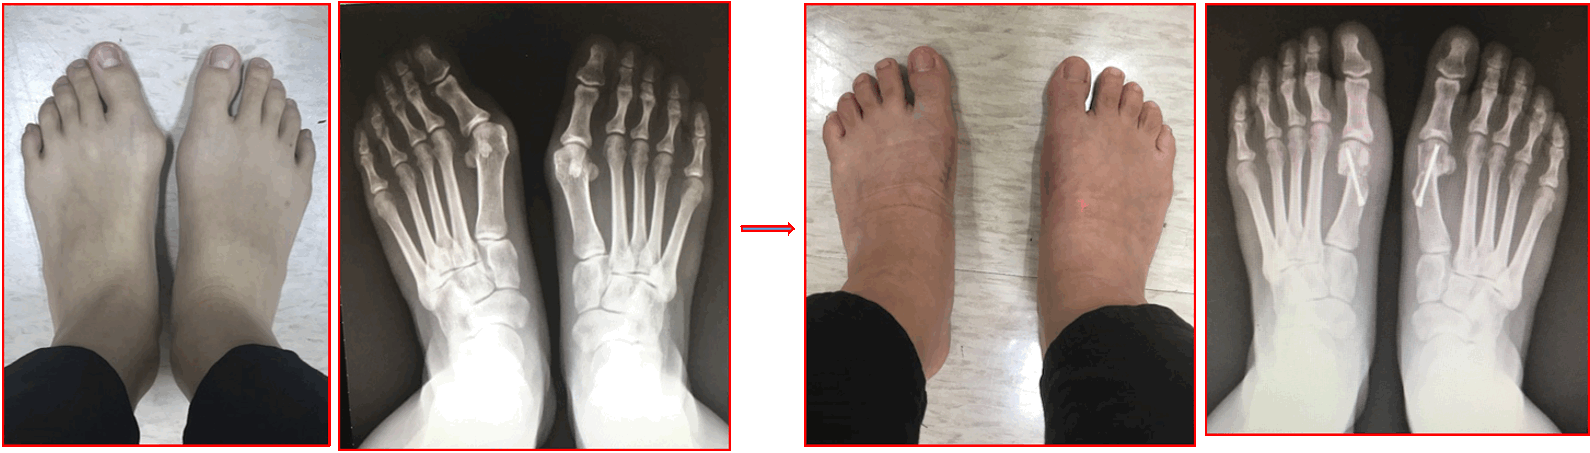

- Big toe valgus deformity correction surgery

9. Big toe correction surgery

e. Hallux Valgus correction surgery